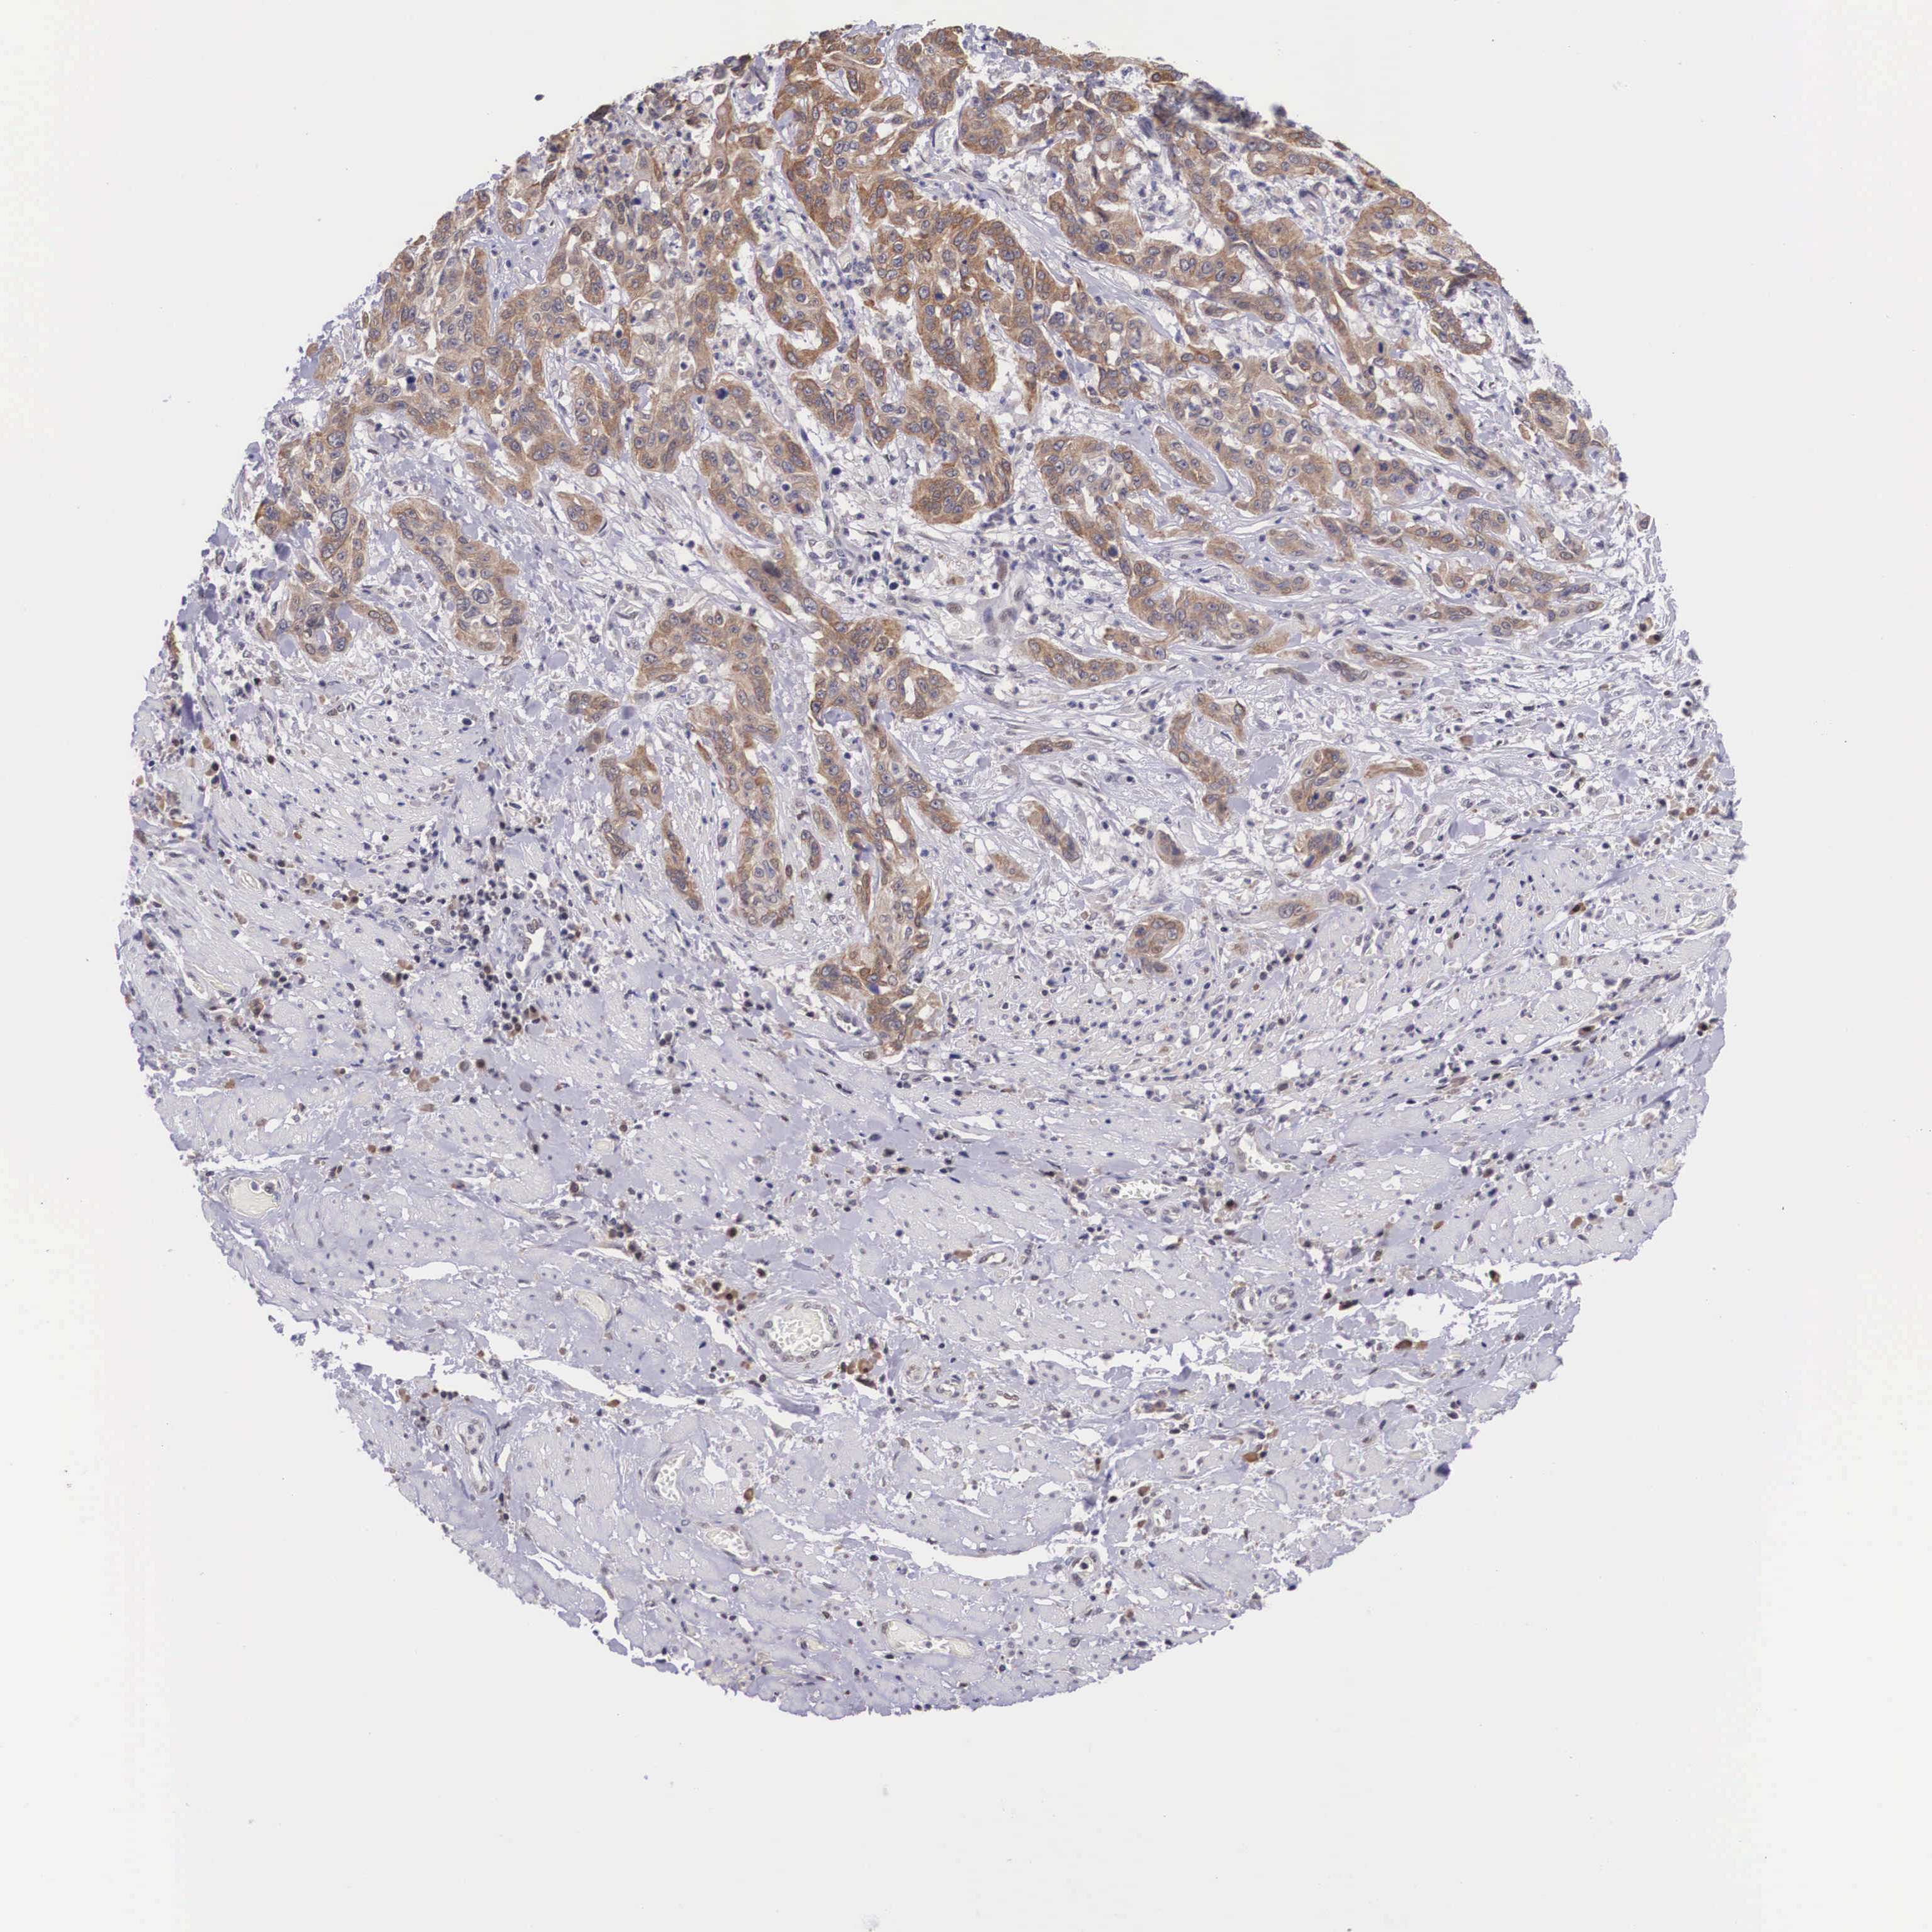

CERVICAL CANCER - Protein expressioni

A mouse-over function shows sample information and annotation data. Click on an image to view it in a full screen mode. Samples can be filtered based on level of antibody staining by selecting one or several of the following categories: high, medium, low and not detected. The assay and annotation is described here.

Note that samples used for immunohistochemistry by the Human Protein Atlas do not correspond to samples in the TCGA dataset.

Antibody stainingi

Antibody staining in the annotated cell types in the current human tissue is reported as not detected, low, medium, or high, based on conventional immunohistochemistry profiling in selected tissues. This score is based on the combination of the staining intensity and fraction of stained cells.

Each image is clickable and will lead to virtual microscopy that enables deeper exploration of all samples and also displays staining intensity scores, fraction scores and subcellular localization as well as patient and tissue information for each sample.

Antibody HPA000662

Staining

High

Medium

Low

Not detected

Intensity

Strong

Moderate

Weak

Negative

Quantity

>75%

75%-25%

<25%

None

Location

Nuclear

Cytoplasmic/membranous

Cytoplasmic/membranous,nuclear

Adenocarcinoma, NOS